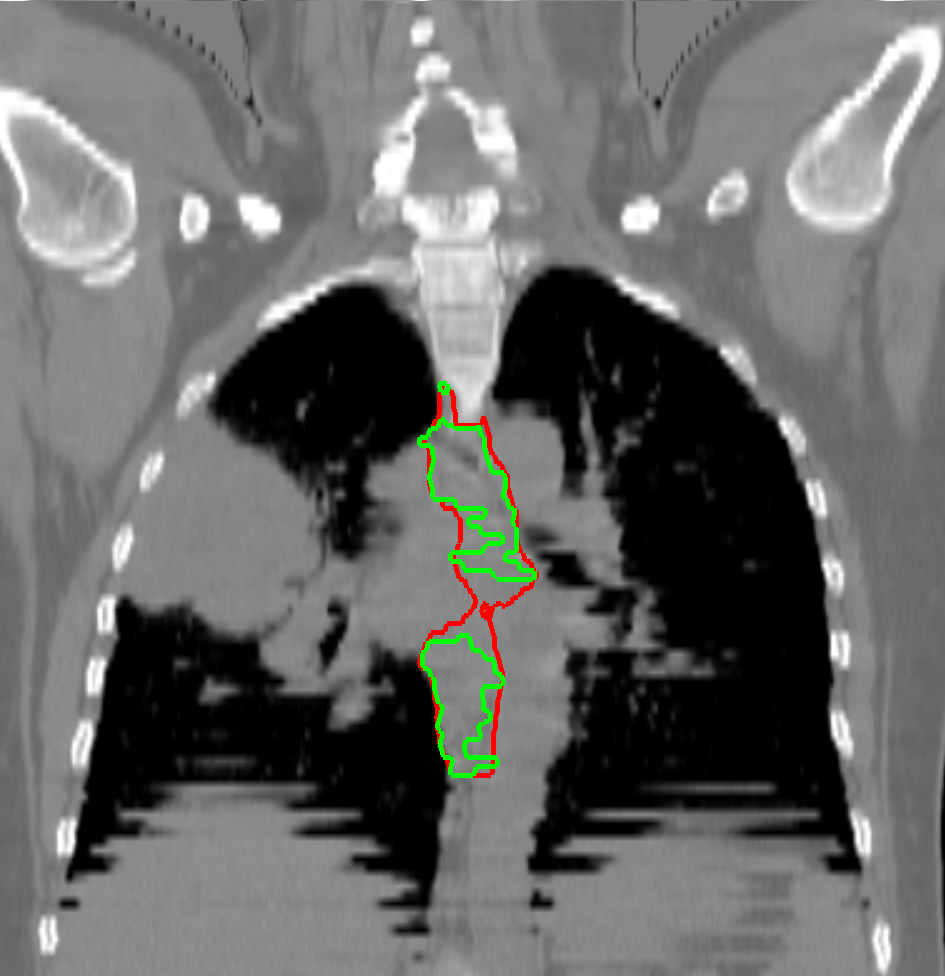

Visual results of our algorithm compared to the reference contour for 6 cases in axial and sagittal view are depicted in Fig. 5. From the sagittal views it can be observed that manual contours are not as smooth as the automatic contours, which could be due to the breathing artifacts. The use of convolutions and post-processing in 3D aids at processing information of the 3D context through several slices, which is reflected in the smoother automatic contours shown in these images. On the other hand, from the axial views we can realize that, despite of the similarity with respect to neighboring tissues, and heterogeneity of the inner region of the esophagus, our automatic system provides contours that are comparable with the reference standard.

Refer to caption a) clinical case 09 sagittal view Refer to caption b) clinical case 13 sagittal view Refer to caption c) clinical case 20 sagittal view

Refer to caption d) clinical case 09 axial view Refer to caption e) clinical case 13 axial view Refer to caption f) clinical case 20 axial view

Refer to caption g) public case 01 sagittal view Refer to caption h) public case 12 sagittal view Refer to caption i) public case 24 sagittal view

Refer to caption j) public case 01 axial view Refer to caption k) public case 12 axial view Refer to caption l) public case 24 axial view

Figure 5: Contouring results for 6 cases in different views. The green line indicates the reference standard, the red line depicts the contour generated by the proposed algorithm.